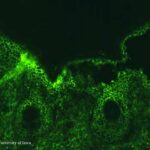

IF Testing. DIF testing of perilesional skin is positive in the vast majority of cases. Two patterns of pemphigus antibody deposition have been described. In most cases, there is full-thickness squamous intercellular substance deposition of IgG. Rarely, IgG may be localized only to the superficial portion of the epidermis . IIF testing of serum reveals |

squamous intercellular substance deposition of IgG in 80% to 90% of cases. |

Pathogenesis. As in pemphigus vulgaris, the autoantibodies of pemphigus foliaceus are pathogenic. During the course of the disease, the antibody levels fluctuate and have some correlation with disease activity. The pemphigus foliaceus antigen, desmoglein 1, is expressed more intensely in the upper layers of the epidermis , which explains the superficial cleavage plane of pemphigus foliaceus. Interestingly, in staphylococcal scalded skin syndrome (SSSS), and its localized form bullous impetigo, the exfoliative exotoxin produced by S. aureus specifically binds and cleaves desmoglein 1, resulting in blister formation at identical levels of the epidermis as pemphigus foliaceus . In addition, desmoglein 1 is concentrated in the upper torso and is less prominent in the buccal mucosa, scalp, and lower torso, correlating with lesion distribution . |